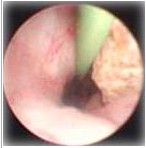

3、输尿管镜下气压弹道碎石取石术:该技术是通过尿道,将镜体进入输尿管内达到结石位置在直视下,用气压弹道撞杆,直接撞击结石,达到碎石的目的。该方法,克服体外碎石对结石周围组织的损伤将外力直接作用于结石,隶属微创的手术范畴,深受广大患者欢迎。